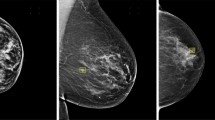

Mammography technique is commonly used for diagnosing breast cancer, but mammography images usually show low contrast which cause difficulties to clinical diagnosis. Therefore, improving the visual quality of mammography images is an important issue. This is a challenging problem, because every mammography image consists of rich textures, including bright areas, dark areas, and textural details. Inspired by bio-inspired neural network, this paper proposes a Bidirectional Spiking Cortical Model (Bi-SCM) from the perspective of neural information fusion to enhance the contrast of bright areas and dark areas adequately, as well as textural details. This goal is achieved by utilizing the Bi-SCM to first enhance a mammography image and its inverse separately. The enhanced results are fused by a new fusion algorithm based on non-subsampled contourlet transform (NSCT) to ensure that both of the contrast of bright areas and dark areas are adequately improved. The textual details are then enhanced by an unsharp masking method which consists of cubic filter and log-ratio operation. Sufficient experiments on mammography images are conducted to evaluate the proposed approach. Experimental results show that the proposed method outperforms state-of-the-art methods on both enhancing contrast and details. Besides, over-enhancement and noise sensitivity are also significantly suppressed.